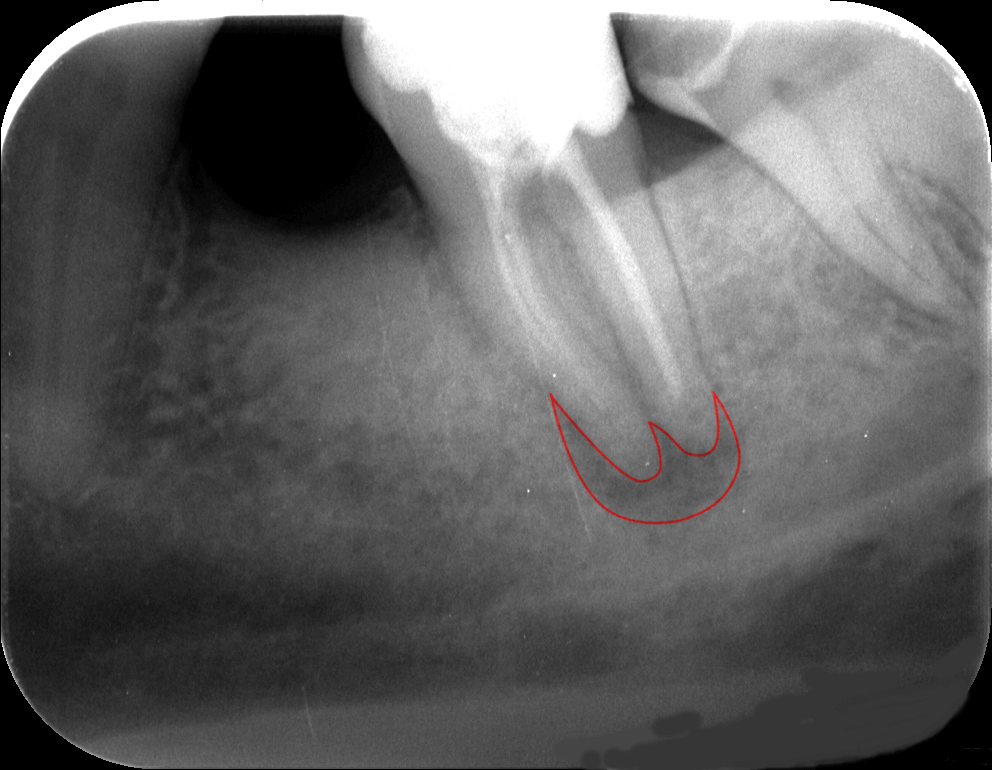

A kiindulási röntgenképen jól látható, hogy a gyökértömés minősége sajnos nem a legmegfelelőbb. Nem sikerült a gyökércsatornákat a teljes hosszon kitisztítani, és a fog gyökércsúcsa körül gyulladás alakult ki. (Az érintett területet pirossal rajzoltuk körbe.)

Sajnos sokszor találkozunk ezzel a problémával. Ami talán még rosszabb, hogy ezek a gyulladások sokszor rejtve maradnak, egészen addig, amíg egyszer csak meg nem fájdul a fog. Ez történt most is: kedves páciensünk igen nagy fájdalmakkal érkezett.